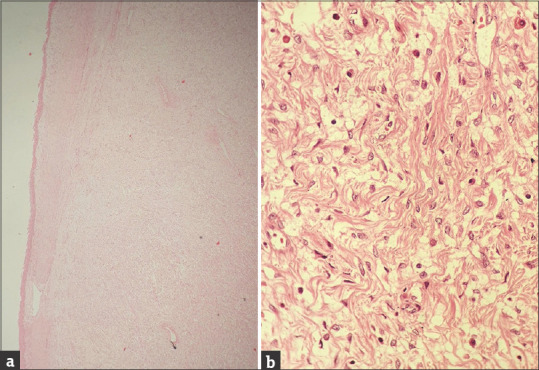

下女性生殖道浅表性肌纤维母细胞瘤是一种罕见的良性间充质肿瘤,近年来才被发现,目前仅报道57例。大多数病例发生在阴道,少数病例发生在宫颈和外阴。它可以表现为息肉样或囊性肿块,少数病例是偶然发现的。它具有独特的形态和免疫组织化学特征。该实体可能模仿女性生殖道的其他良性和恶性状况,因此构成诊断挑战。在这里,我们描述了一例宫颈浅表肌成纤维细胞瘤患者,其表现为阴道出血和宫颈息肉。形态学和免疫组织化学检查结果有助于最终诊断。意识到这种罕见的良性实体可以帮助我们将浅表肌成纤维细胞瘤与许多侵袭性实体区分开来,从而防止根治性手术。

Superficial myofibroblastoma of the lower female genital tract is a rare and recently identified benign mesenchymal tumor with only 57 cases reported till now. Majority of the cases are described in the vagina and few cases in the cervix and vulva. It may present as a polypoid or cystic mass, and few cases are detected incidentally. It has a unique morphology and immunohistochemical features. The entity may mimic other benign and malignant conditions of the female genital tract and hence pose a diagnostic challenge. Here, we describe a patient with cervical superficial myofibroblastoma who presented with bleeding per vaginum and polyp in the cervix. Morphology and immunohistochemical findings helped in the final diagnosis. Awareness of this rare benign entity can help us to differentiate superficial myofibroblastoma from many aggressive entities and thus prevent radical surgeries.